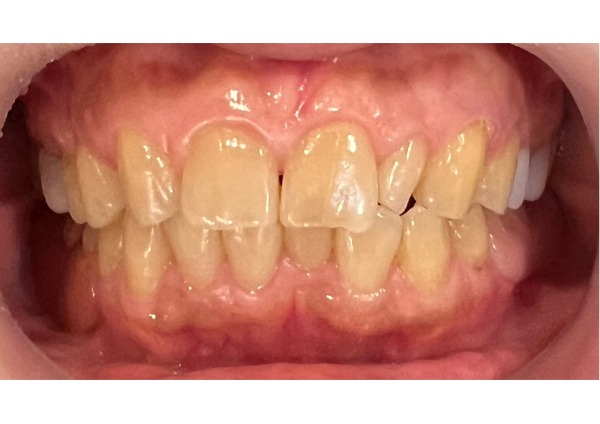

こちらはノンクラスプデンチャーを口腔内に装着した正面写真です。